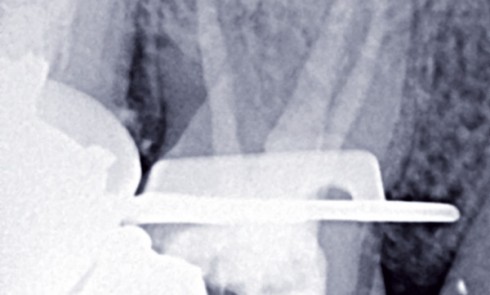

Article réservé à nos abonnés Sécuriser nos mises en forme canalaire

Sécuriser nos mises en forme canalaire, c’est tout simplement suivre, encore et toujours, les objectifs établis par Schilder depuis plusieurs...